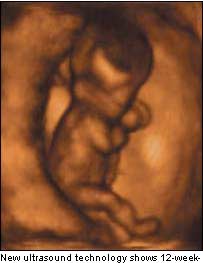

据BBC消息,利用一种能够生成3维图像的新型超频成像仪器,伦敦保健门诊由坎贝尔教授领导的扫描技术专家得到了只有12周的胎儿在子宫中“走动”的图像。

过去的扫描仪(即B超)只能得到2维的图象,测量出胎儿的发育指数;而这种新型超频成像器可以观测、显示出胎儿早期的复杂行为和举止。

专家除了得到12周大的胎儿在子宫中“走动”的图像外,还得到了胎儿打呵欠、揉眼睛的图像。通过这种仪器,还发现胎儿长到26周大就几乎具备了人类的所有典型举动,包括抓骚、微笑、哭泣、打呃、吸奶等。

通常,孕妇根本感觉不到12周胎儿的胎动,因而此前人们也根本不知道12周的胎儿能在子宫中伸胳膊、蹬腿、转身。 多数医生认为胎儿要长到26周时,眼皮才能合拢,而实际上,坎贝尔教授的图片显示,胎儿在18周就可以睁开眼睛。 早些时候,坎贝尔教授领导的专家组发布新闻,通过新技术,他们得到胎儿微笑的图像。教援把有关图像编辑成一本名为《看着我长大》的书。在此之前,人们认为微笑是新生儿出生6周后才有的表情。